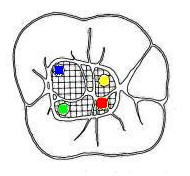

Primer Molar Inferior Esta pieza dentaria es la más voluminosa de la arcada. Posee por general dos raíces bien definidas una mesial y otra distal, ambas aplanadas en sentido mesiodistal. La raíz mesial presenta una curvatura acentuada, mientras que la distal puede ser algo curva o recta. Cuando tiene tres conductos el mas amplio es el distal con una sección oval y su curvatura es suave o recta. Si presenta cuatro conductos la raíz distal contendrá dos de ellos y son de diámetro más pequeño y en caso de presentar dos conductos, ambos son amplios. Segundo Molar Inferior Es de menores proporciones que el primer molar y sus raíces en general son dos y diferenciadas como en el primer molar ,así como también pueden presentarse fusionadas parcial o totalmente. |